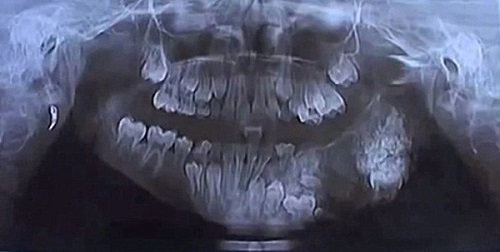

Old  Default Cậu bé 7 tuổi có 80 chiếc răng thừa

Được chuẩn đoán mặc căn bệnh u răng – một dạng u lạ gây ảnh hướng tới xương hàm và lợi, cậu bé 7 tuổi đã phải trải qua một cuộc phẫu thuật để nhổ bỏ 80 chiếc răng thừa.

Mặc dù mới chỉ bước sáng tuổi thứ 7 nhưng một cậu bé sống tại thành phố Mumbai, Ấn Độ đã có một hàm răng "khủng" với số lượng lên tới hơn 100 cái, ước tính nhiều gấp gần 3 lần so với người thường. Cuối cùng, sau ca phẫu thuật kéo dài 4 tiếng đồng hồ, các bác sĩ đã nhổ bỏ thành công 80 chiếc răng thừa ra khỏi miệng cậu bé.

Được biết, cậu bé không tiết lộ danh tính này đã được gia đình đưa tới Bệnh viện Maharaja Yashwantrao ở thành phố Mumbai sau khi miệng bị sưng to trong khoảng thời gian kéo dài. Qua kiểm tra sơ bộ, các bác sĩ đã phát hiện gần trăm khối u có hình dáng và cấu tạo giống răng đang thi nhau mọc lên từ hàm trên của cậu bé.

Theo các bác sĩ nha khoa của Bệnh viện Maharaja Yashwantrao, những chiếc răng thừa này tập hợp lại với nhau, tạo thành áp-xe trong miệng cậu bé. Các kết quả xét nghiệm, chụp chiếu khác cho thấy, cậu bé đã mắc căn bệnh u răng, một dạng u lạ gây ảnh hướng tới xương hàm và lợi. Và trường hợp mắc bệnh sớm như cậu bé này được đánh giá là hiếm gặp.

Hình chụp X-quang xương răng của cậu bé.

Những bệnh nhân bị u răng thường mọc các khối u có hình dáng và cấu tạo giống răng. Do được hình thành từ men và ngà răng nên người ta vẫn thường coi nó là răng thừa.

Sau khi xử lý áp-xe, các bác sĩ đã tiến hành nhổ bỏ toàn bộ số răng thừa ra khỏi hàm trên của cậu bé.